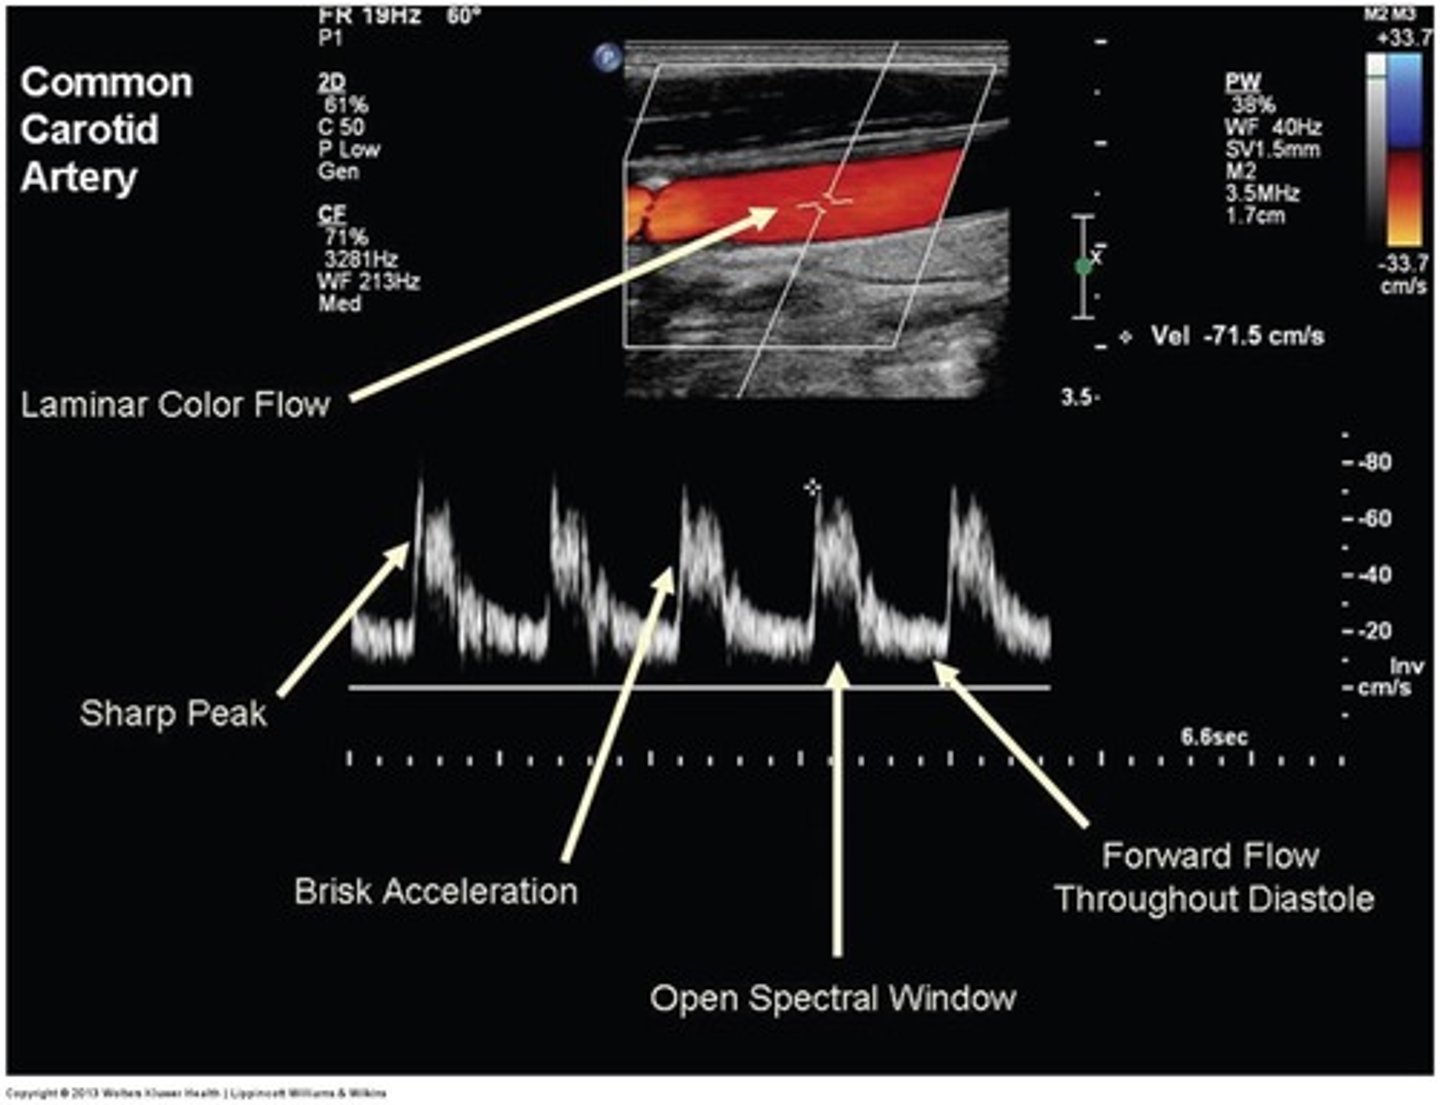

Which artery does this waveform best represent?

Prox ICA

CCA

Which of the following is NOT a characteristic of normal Doppler waveform contour?

a. brisk systolic acceleration

b. sharp systolic peak

c. increased spectral broadening

d. clear spectral window

Why do Doppler waveforms in the common carotid arteries display a contour suggestive of relatively low-resistance flow?

a. 70% of its flow supplies the ICA

b. 90% of its flow supplies the ICA

c. 70% of its flow supplies the ECA

d. 90% of its flow supplies the ECA